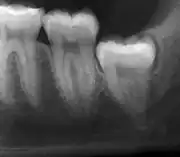

Impacted 2nd molar (red arrow) with developing wisdom tooth (green arrow)

There is no standard to screen for wisdom teeth. It has been suggested, absent evidence to support routinely retaining or removing wisdom teeth, that evaluation with panoramic radiograph, starting between the ages of 16 and 25 be completed every 3 years. Once there is the possibility of the teeth developing disease, then a discussion about the operative risks versus long-term risk of retention with an oral and maxillofacial surgeon or other clinician trained to evaluate wisdom teeth is recommended. These recommendations are based on expert opinion level evidence.[19] Screening at a younger age may be required if the second molars (the "12-year molars") fail to erupt as ectopic positioning of the wisdom teeth can prevent their eruption. Radiographs can be avoided if the majority of the tooth is visible in the mouth.